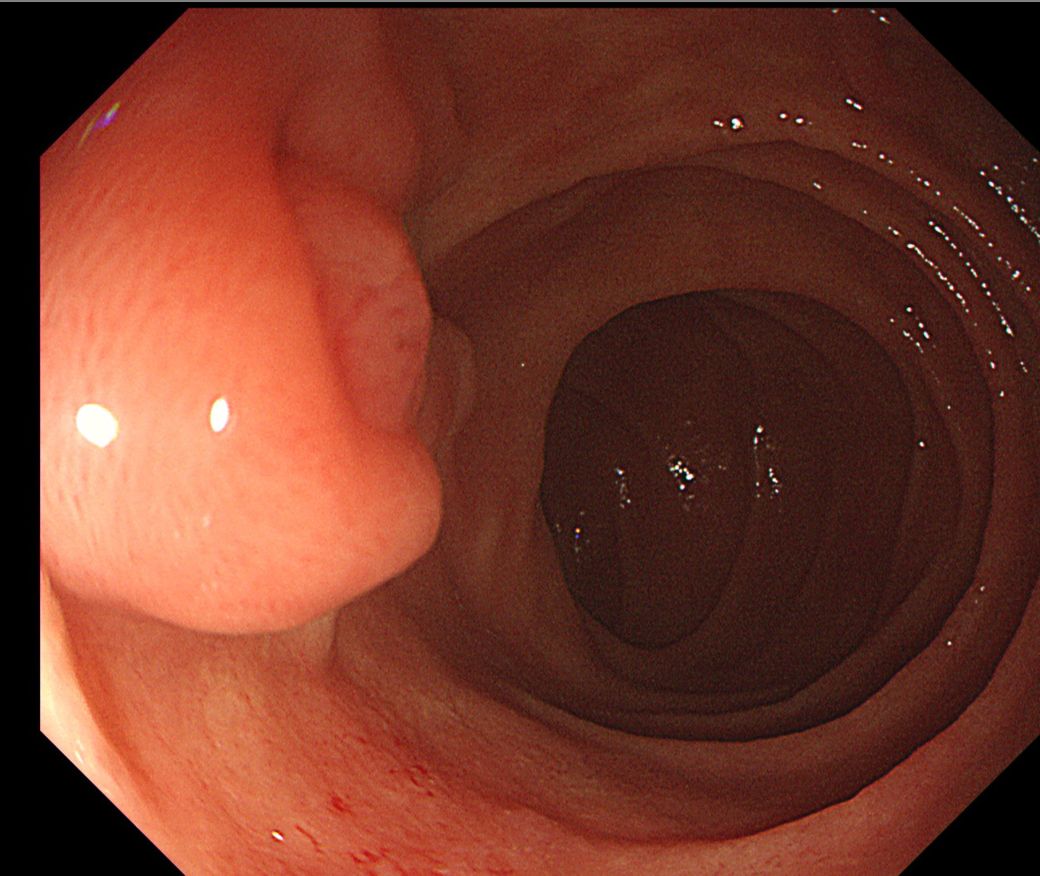

아래 사진이 바터팽대부가 맞나요? 바터팽대부는 정상인가요?

• 1번 째 사진

박터팽대부는 크게 이상이 있는 소견으로 판단되지는 않습니다. 바터팽대부는 실제로 돌출이 되어있기에 용종등과 육안상으로 명확히 감별이 안될수 있어 의심이 된다면 조직검사를 하거나 단기간 추적검사를 하는 것을 권장드립니다.